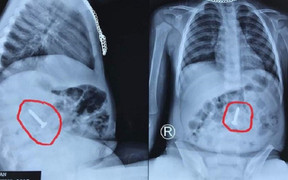

Người đàn ông bị đau bụng, khó tiêu, đi khám mới biết nuốt cả chiếc bàn chải dài gần 20 cm lúc nào không hay.